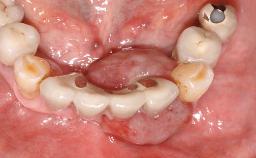

Surgical treatment of a 68-year-old female patient with a distal extension situation in the left mandible. As the CBCT analysis reveals, the bone crest anatomy in the area is not ideal and necessitates an augmentation procedure to achieve a good long-term prognosis for the planned implants and their prostheses.

Case Type Extended Space

Jaw Mandible

Area Posterior

# of Teeth 3

# of Implants 3